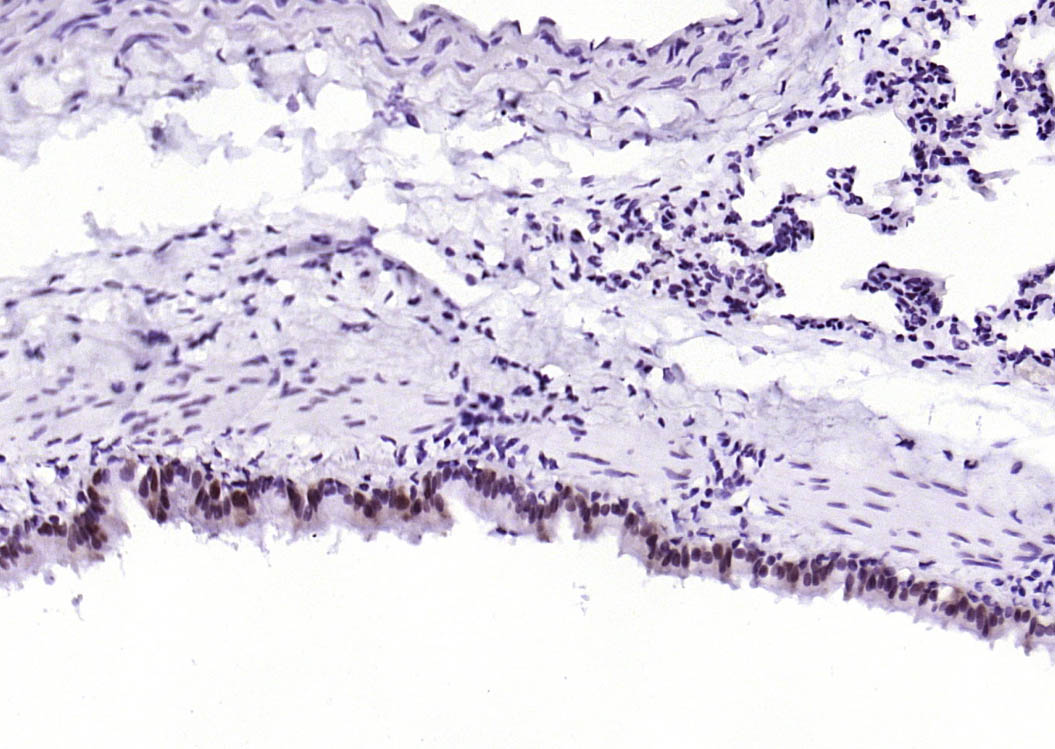

| 产品应用 | WB=1:500-1000, IHC-P=1:50-200, IHC-F=1:50-200, IF=1:50-200 Not yet tested in other applications. |

| {IHC-P} | {1:50-200} |

| {IHC-F} | {1:50-200} |